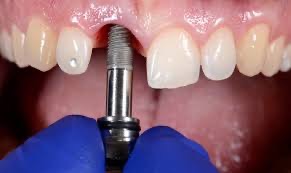

二、手術階段(1次)

• 植入人工牙根:將植體放入缺牙位置的牙骨中。

• 印製個人牙拖模型、拍攝根尖X光片確認植體與齒槽骨狀況、裝戴上癒合帽(局部麻醉下)